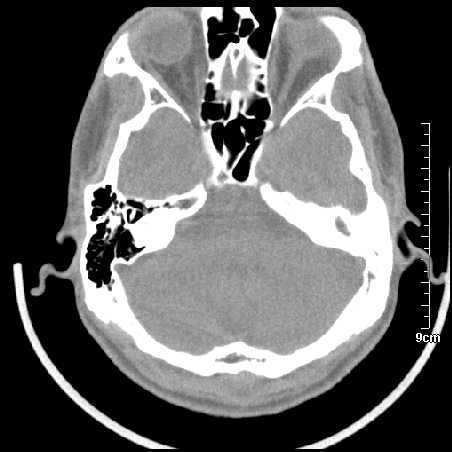

病例2

m/27

左侧慢性中耳炎伴胆脂瘤形成。

左中耳乳突炎合并胆脂瘤形成